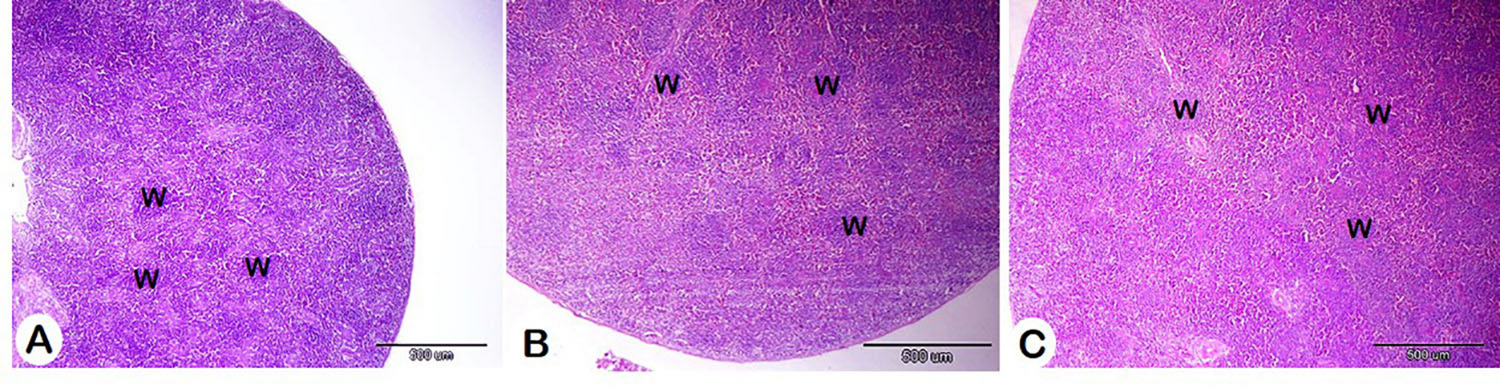

Fig. 7

Histomorphometry of the effect of different concentrations of HM on the spleen. A: Control group, B: HM group 1, and C: HM group 2. White pulp (W). H&E stain.